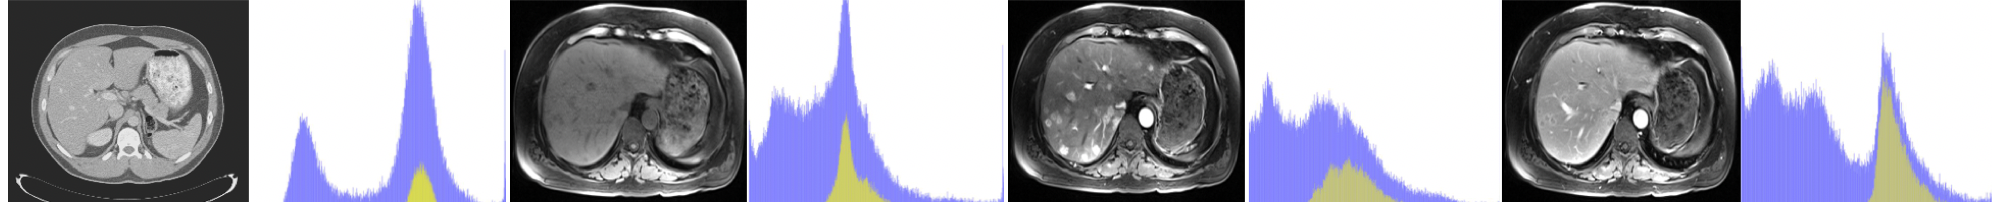

3.2.6 A. Robust Domain Adaptation

Refer to caption

Figure 6: Two examples of content-only images via disentangled representations for multi-phasic MR. first row: original images, second row: content-only images.

A CycleGAN model was not able to handle such large variety in the multi-modal target domain e.g. multi-phasic MR. However, for our model, the shared content space provided a robust representation for anatomical information in multi-phasic MR; thus it remained effective even faced with the multi-modal target domain (see Fig.  6 and Table  3).